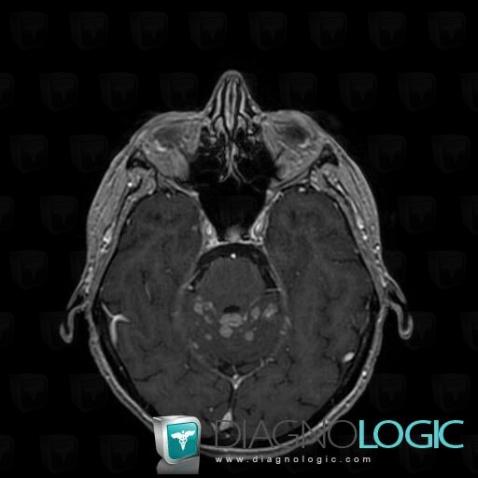

Les images ci-dessous illustrent ce dossier pour les diagnostics Carcinose méningée, Méningite carcinomateuse, pour les modalités (IRM)

Voici les informations spécifiques à l'image clé ci dessus:

- Diagnostic Méningite carcinomateuse, Localisation(s) Espaces peri cérébraux infratentoriels, comportant les gammes Réhaussement méningé diffus

Voici les informations spécifiques à l'image clé ci dessus:

- Diagnostic Carcinose méningée, Localisation(s) Autres nerfs craniens, comportant les gammes Lésion des nerfs craniens

Voici les informations spécifiques à l'image clé ci dessus:

- Diagnostic Carcinose méningée, Localisation(s) Hypophyse et région parasellaire, comportant les gammes Lésion de la tige pituitaire